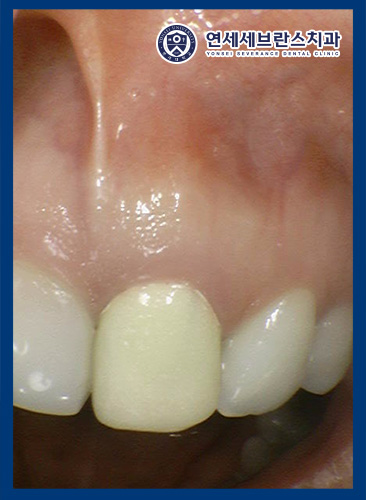

26.01.22

<치은부종 감소>

신경치료를 진행하면서

염증으로 인해 생겨났던

뾰루지가 점점 사라지면서

치은부종이 감소한 것을

확인할 수 있었습니다.